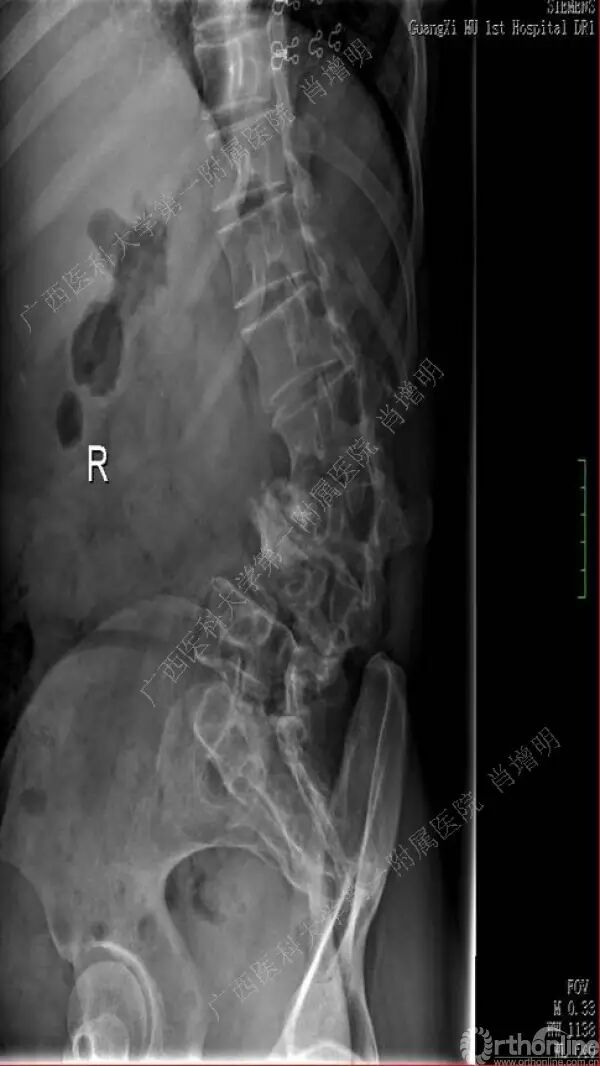

退变性脊柱侧凸是由于椎间盘退变后继发小关节退变,椎管和神经根管容积变化以及脊柱失稳,畸形等病理改变,以疼痛和神经压迫症状为主要表现的常见疾病。

退变性脊柱侧凸多发于50岁以上的中老年群体,是现代常见的老年疾病。多年来,针对该病的临床研究一直没有停步,广西医科大学第一附属医院肖增明教授细致地介绍了该病的诊疗进展。